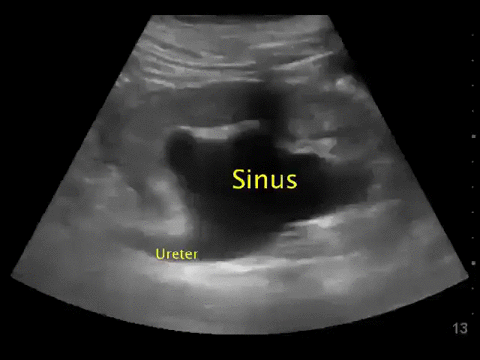

Point-of-care abdominal sonography is performed and the following representative image is obtained by examining the left flank.

What is the most likely source of sepsis in this patient?